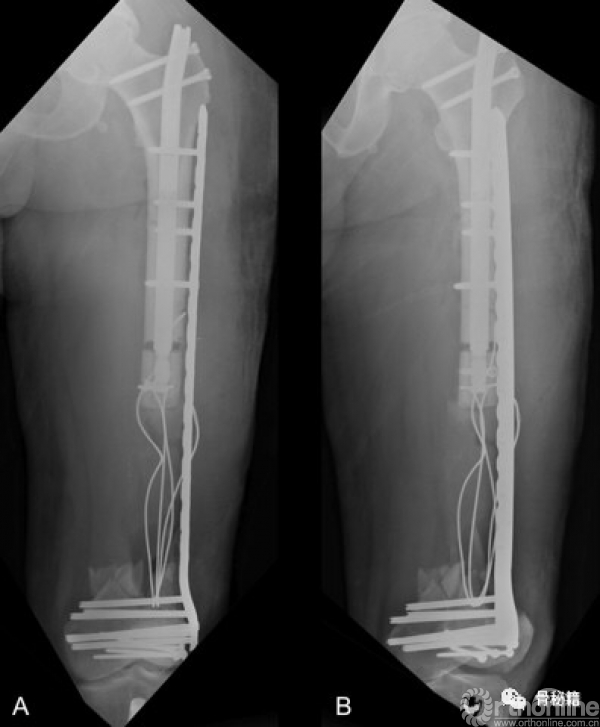

按照此路径进行了骨延长后,可见骨的生长,截骨块已经延长了一部分

此时去掉了髓内钉远端的锁定,将髓内钉稍微短缩了一些,露出远端的锁定孔

将捆绑线穿过髓内钉的远端锁钉控,继续延长到了髓内钉的极限位置

将滑轮组翻转,一端再髓内捆绑到髓内钉的远端,另外一段经过远端锁定孔后固定于骨折块,然后进行髓内钉的短缩,就通过滑轮原理继续进行了骨折块的搬移

通过漫长的搬移,终于骨折断端接触了